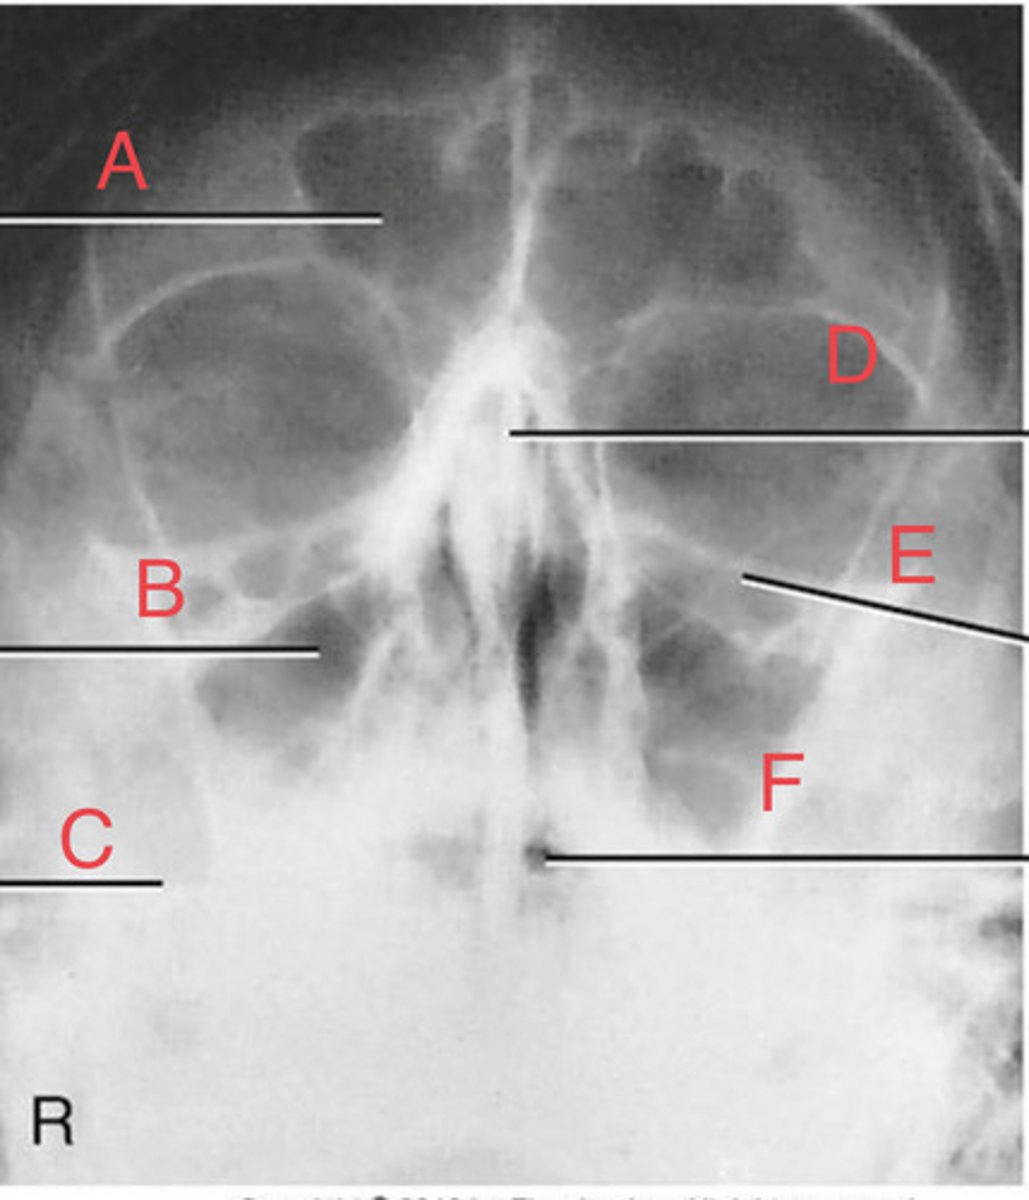

Waters sinus method

What projection?

r. frontal sinus of the frontal bone

A.

R. Maxillary sinus of maxilla

B.

R. petrous ridge of temporal bone

C.

bony nasal septum

D.

L. inferior orbital fissure of sphenoid bone

E.

Sphenoid sinus of sphenoid bone

F.

bony nasal septum

E.